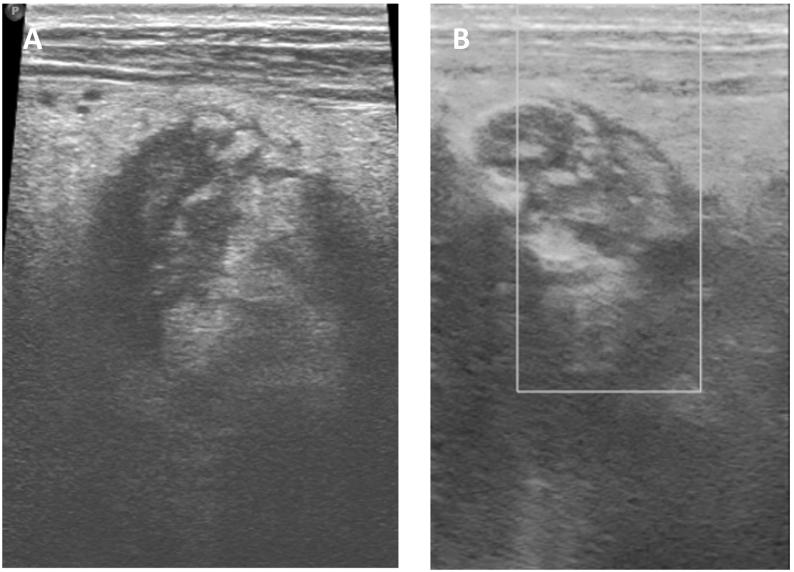

We present a case report of a 50-year-old woman with type 2 diabetes and psychiatric illness presented with 2 days of vomiting, abdominal pain, and dehydration. Physical examination showed a tender mass in the abdomen and imaging confirmed a twisted spleen with a thrombosed splenic vein, leading to a successful emergency splenectomy. The patient had an uncomplicated recovery and was discharged with post-splenectomy protocol.

Splenic torsion, a rare occurrence primarily observed in children. Clinical diagnosis is aided by palpable abdominal masses and confirmed by radiological imaging. The gold standard diagnostic tool is contrast-enhanced computed tomography (CT), whereas Ultrasonography (USG) is equally good in early assessment. Early identification is crucial to salvage the spleen. Management options include detorsion, splenopexy, or splenectomy depending on the organ viability. Elective splenopexy has emerged as a proactive measure, particularly in children, to prevent complications.

我们报告一例50岁2型糖尿病合并精神疾病的女性患者,出现2天呕吐、腹痛及脱水症状。体格检查发现腹部有压痛性肿块,影像学检查证实脾脏扭转伴脾静脉血栓形成,遂成功实施急诊脾切除术。患者恢复顺利,按脾切除术后方案出院。

脾扭转是一种主要在儿童中观察到的罕见情况。腹部可触及肿块有助于临床诊断,影像学检查可确诊。金标准诊断工具是增强计算机断层扫描(CT),而超声检查(USG)在早期评估中同样有效。早期识别对于挽救脾脏至关重要。治疗方案包括根据器官活力进行扭转复位、脾固定术或脾切除术。选择性脾固定术已成为一种积极措施, 尤其在儿童中,以预防并发症。